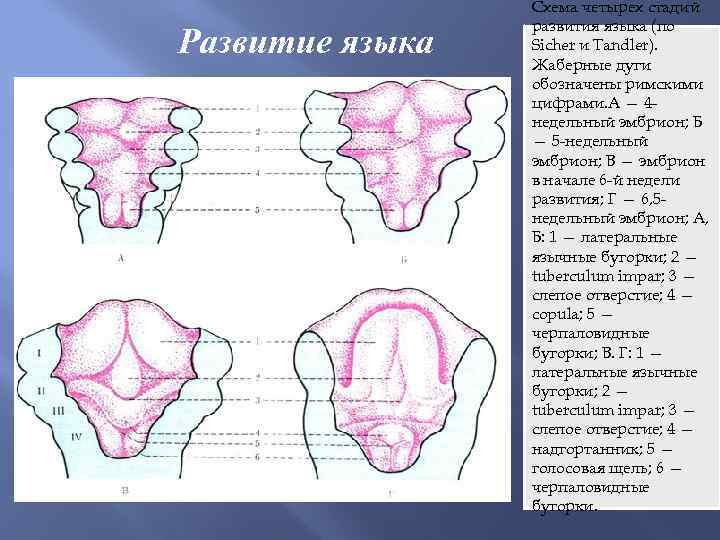

Развитие языка Схема четырех стадий развития языка (по Sicher и Tandler). Жаберные дуги обозначены римскими цифрами. А — 4 недельный эмбрион; Б — 5 -недельный эмбрион; В — эмбрион в начале 6 -й недели развития; Г — 6, 5 недельный эмбрион; А, Б: 1 — латеральные язычные бугорки; 2 — tuberculum impar; 3 — слепое отверстие; 4 — copula; 5 — черпаловидные бугорки; В. Г: 1 — латеральные язычные бугорки; 2 — tuberculum impar; 3 — слепое отверстие; 4 — надгортанник; 5 — голосовая щель; 6 — черпаловидные бугорки.

Развитие языка Схема четырех стадий развития языка (по Sicher и Tandler). Жаберные дуги обозначены римскими цифрами. А — 4 недельный эмбрион; Б — 5 -недельный эмбрион; В — эмбрион в начале 6 -й недели развития; Г — 6, 5 недельный эмбрион; А, Б: 1 — латеральные язычные бугорки; 2 — tuberculum impar; 3 — слепое отверстие; 4 — copula; 5 — черпаловидные бугорки; В. Г: 1 — латеральные язычные бугорки; 2 — tuberculum impar; 3 — слепое отверстие; 4 — надгортанник; 5 — голосовая щель; 6 — черпаловидные бугорки.